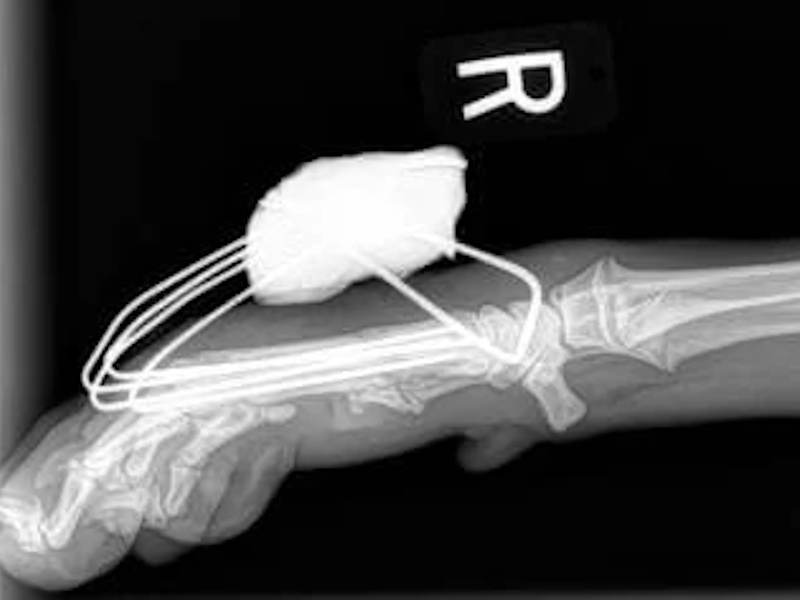

Carpal Hyperextension

- Pan-Carpal Arthrodesis: $6,500 - $8,000+

- Partial Carpal Arthrodesis: $5,250+

- Pan-tarsal Arthrodesis: $6,500 - $8,500+